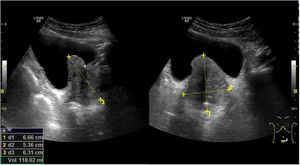

La ecografía por vía abdominal permite no solo la medición de tamaño prostático, es decir los ejes y el volumen, sino también la forma de crecimiento, valorando si es un crecimiento uniforme o principalmente del lóbulo medio.

Para la medición de tamaño prostático se utiliza la doble pantalla para poder medir en el corte longitudinal el eje craneocaudal y en el corte transversal el eje anteroposterior y el transversal de la próstata, y de esta manera poder hallar el volumen prostático. La clasificación del crecimiento prostático es5 (fig. 3 y video 4):

- -

Grado I: Eje AP 30-38mm y volumen 20-36cc

Grado II: Eje AP 38-45mm y volumen 36-60cc

Grado III: Eje AP 45-55mm y volumen 60-90cc

Grado IV: Eje AP>55mm y volumen >90cc